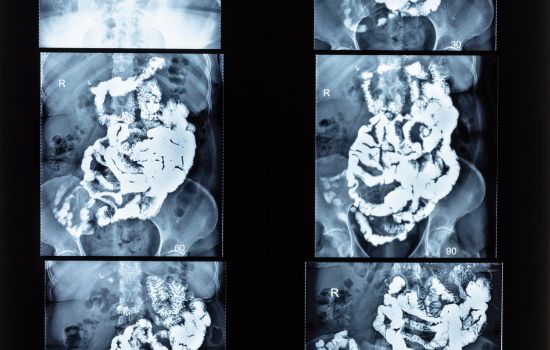

Die Kolontransitzeit oder Darmpassagezeit ist die benötigte Zeit, damit Nahrungsreste den Verdauungstrakt vom Magen bis zum Rektum durchlaufen. Eine verlängerte Kolontransitzeit kann ein Hinweis auf eine Obstipation (Verstopfung) sein, was verschiedene Ursachen haben kann, darunter Ernährungsgewohnheiten, Bewegungsmangel, Dehydratation und verschiedene medizinische Zustände.

Weiterlesen: Kolontransitzeit oder Darmpassagezeit - Hinton-Test